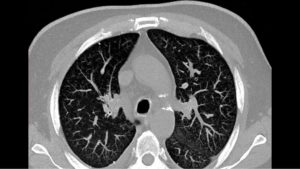

Расшифровка снимков происходит в тот же день. Полученные изображения анализирует врач-рентгенолог, который и выдает заключение. Определить верный диагноз непросто, ведь среди нескольких десятков оттенков черного, серого и белого необходимо вычленить несоответствующий норме и интерпретировать результат. Представим Вашему вниманию несколько фото томографии грудной клетки:

Выпот (красные стрелки) в обеих плевральных полостях.